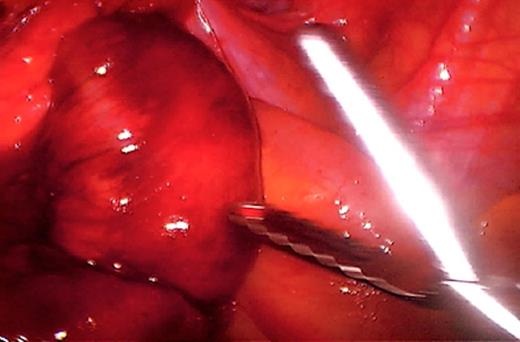

The initial management consisted of a NG tube insertion, IV hydration, and serial abdominal exams. Later, the patient was taken to the operating room due to the significant worsening of her pain. The abdomen was insufflated via the umbilicus with a Veress needle and a 5mm port was placed. Extensive adhesions were visualized throughout the pelvis which was carefully divided. The majority of the small bowel was normal in appearance (Fig. 3), but a segment of 1.5 feet was ischemic and surrounded by dense adhesions (Fig. 4).

This segment was resected and a side-to-side anastomosis was performed (Fig. 5 & 6). On POD 1 bowel function returned and she was started on a clear liquid diet. On POD 2 the patient was started on a regular diet and was discharged home the following morning. On POD 8 she was seen in the office and by then had returned to her baseline level of functioning.